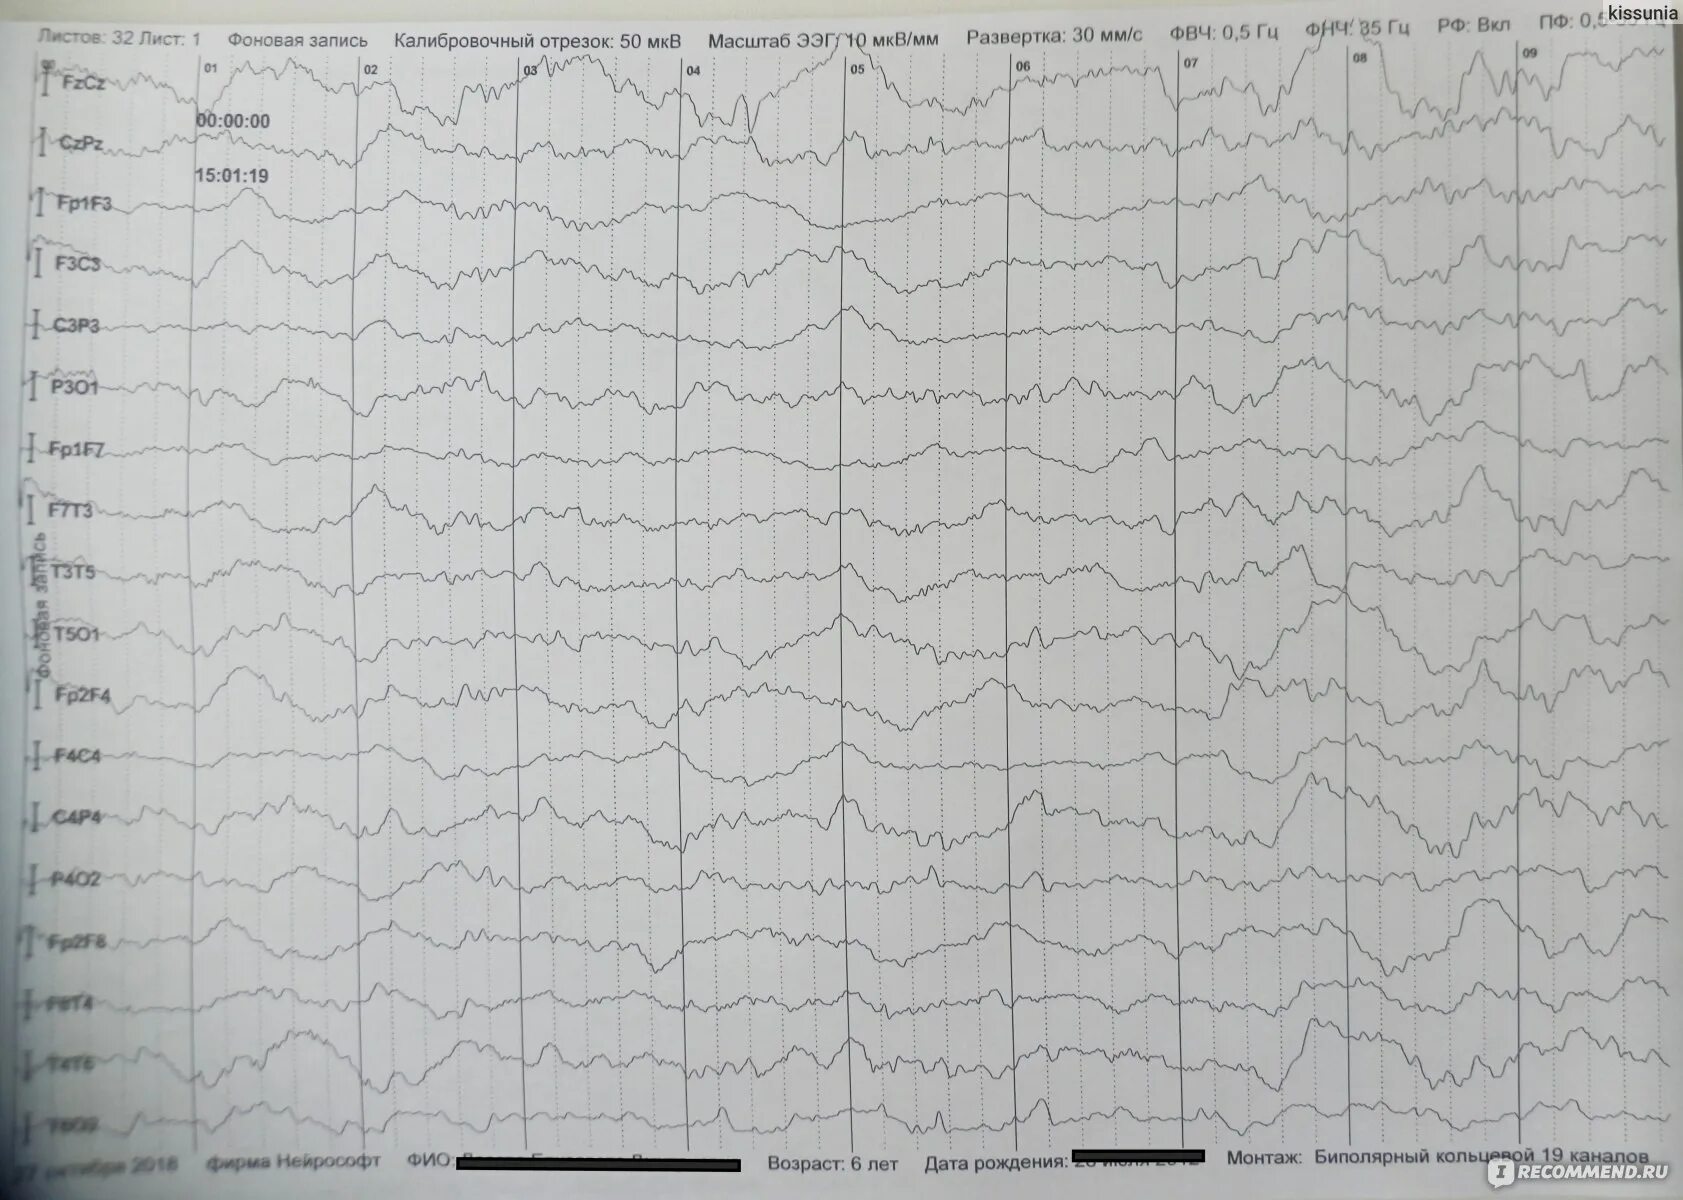

Ээг мониторинг головного мозга